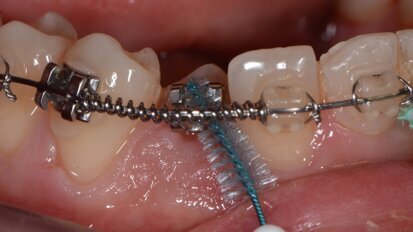

Progettazione della terapia chirurgica dell’eruzione passiva alterata: l’evoluzione digitale

L’eruzione passiva alterata rappresenta una condizione molto frequente nei giovani e negli adulti ed è stata descritta ampiamente in letteratura sia per ...